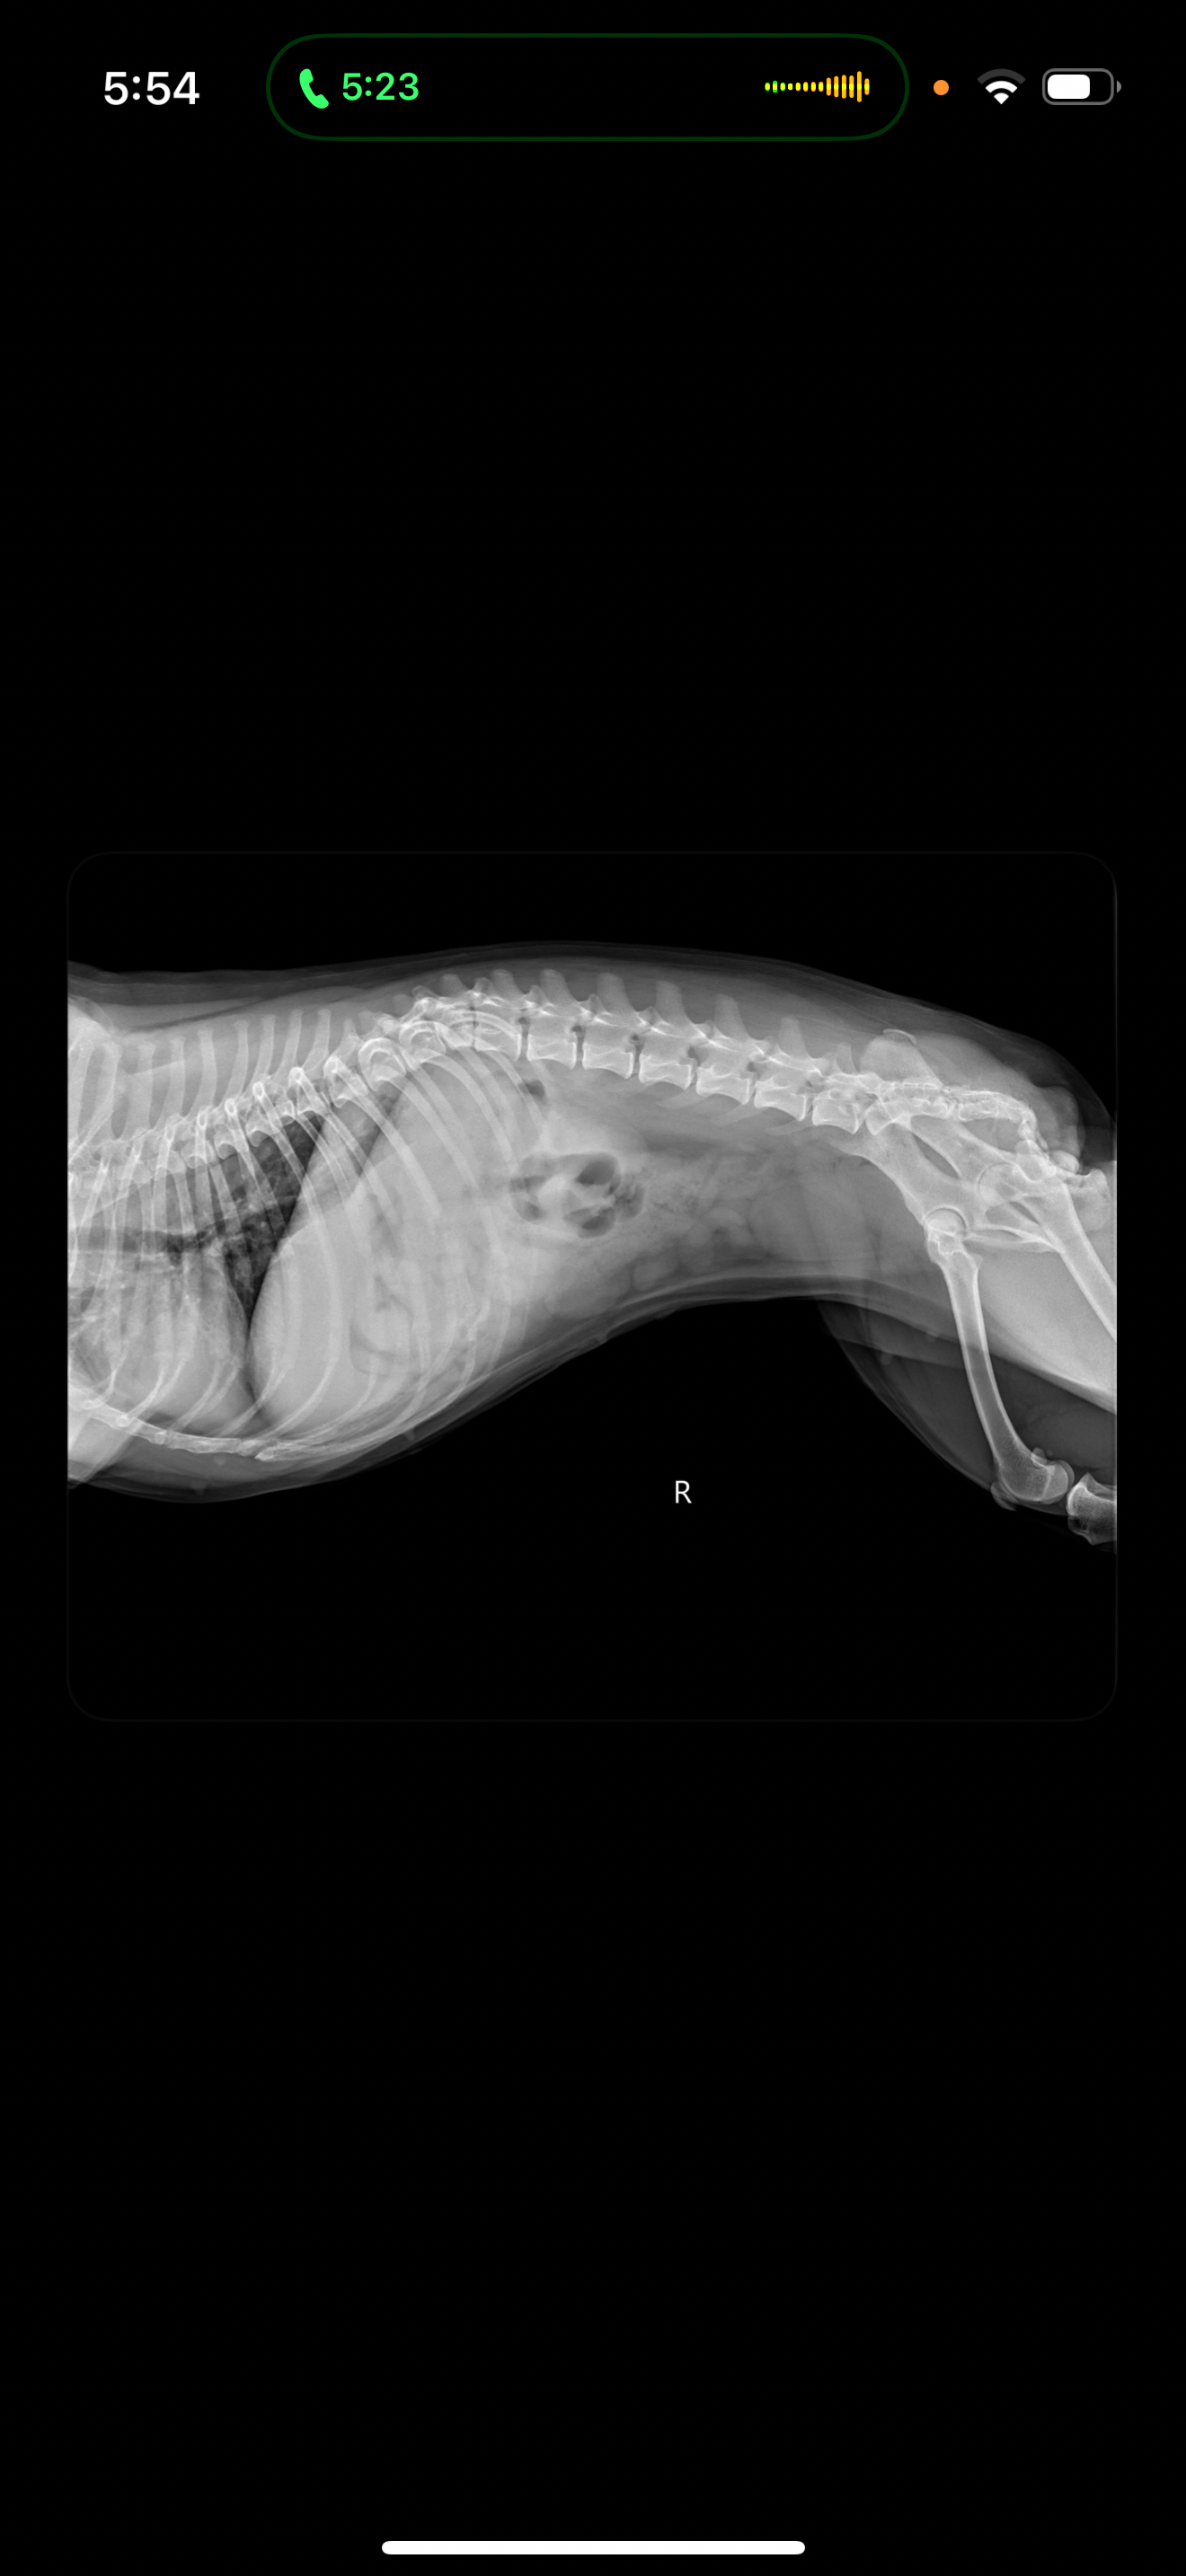

Out of nowhere, Skyler became very ill—she started vomiting, had diarrhea, and lost all interest in food. She was shaky, lethargic, and couldn’t even keep water down. I rushed her to the vet, where they discovered a blockage in her intestine that wasn’t moving, even after fluids and IVs. The vet recommended emergency exploratory surgery to find the cause. During the operation, I got the call every pet parent dreads: Skyler’s heart had stopped. The team performed CPR and, thankfully, brought her back. They found a large mass in her intestine that had caused part of it to die off. The vet quickly removed the damaged section and stitched the healthy ends together, saving her life.

After surgery, Skyler was transferred to an ER vet for close monitoring due to the intensity of her ordeal. She’s stable now, but she’s facing an abnormal heart rhythm and pancreatitis from all the inflammation. She’ll need ongoing medications and care to recover fully. Any funds received will go directly toward paying for her surgery, ER care, and the medications she needs to heal. Skyler means the world to me, and I’m asking for help from anyone who can support her recovery. Your kindness will make a real difference in her life and mine.